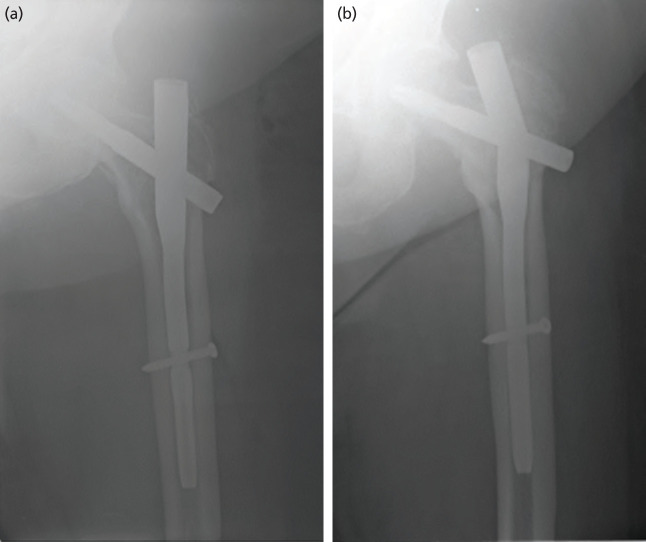

Introduction: Intramedullary nailing in the management of hip fractures is gaining in popularity. Our study aims to determine if there are any clinical and radiological differences between the Proximal Femoral Nail Antirotation II (PFNA II) and the Dynamic Hip Screw (DHS) in the management of stable intertrochanteric (IT) femur fractures. Materials and methods: This is a single blinded prospective randomised controlled trial of 33 patients, aged above 60, comparing the use of the PFNA II and the DHS for the treatment of stable IT femur fractures in a single tertiary centre with an established ortho-geriatric co-managed hip fracture care pathway.

Results: Of the 33 patients enrolled, 18 patients were treated with the DHS and the rest with the PFNA II. The two groups had similar demographic profiles and pre-operative radiological parameters. There was no statistical difference between the two groups in terms of intra-operative bleeding, post-operative pain score and total surgical time. The median Harris Hip and Parker Mobility Scores for the DHS group were non-inferior compared to the PFNA II group. Surgical time, blood loss, post-op radiological parameters and functional outcomes including time to ambulation were similar in both groups.

Conclusion: We recommend the use of the DHS for stable IT fracture patterns in view of its cost savings and equivalent functional and radiological outcomes.